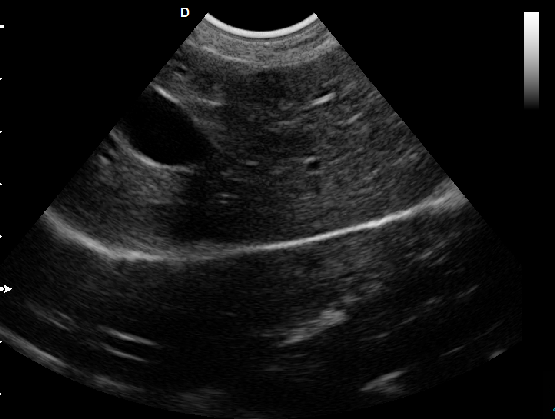

P5-VET獸用彩超機脊椎檢查圖

脊椎檢查:

脊柱裂的預防和確診,一般在動物懷孕以后定期給動物做超聲檢查,通過超聲、超聲檢查可以早期發現動物胎兒是否合并了脊柱裂或是神經管閉合不全。